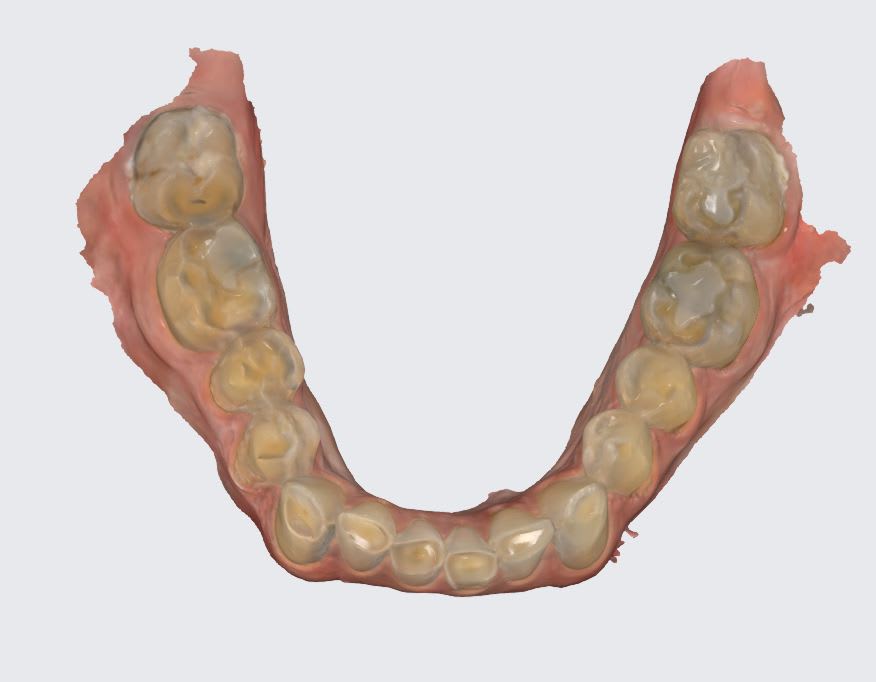

Bon, américain de 70 ans, ressemble à Castex, donc la bombasse j'ai pas sous la main, usure étrange à 60° maxillaire palatine sur les molaires. Vient 15 jours, a pas les moyens de se faire traiter aux USA, ne demande pas la lune mais de pouvoir mâcher des burger sans avoir mal. je me demande si une restauration postérieure peut faire l'affaire, suis tellement étonné de la forme de l'usure des mol maxillaires.

Wakrap , ton Américain a un sur guidage ant avec en plus un sur-contact cingulaire en fin de mvt de fermeture .

quand tu es comprimé des atm , il faut que tu te trouves du jeux pour te détendre un petit peu , et ce jeux , il l a trouvé en fracassant les molaires ce qui lui permet d avoir une liberté droite gauche .

en gros le jeux antero post qu il a perdu , il l a compensé en se créant un jeux latéral .

si elles sont plates , ils s en accommodera .

il faut , pour compenser , que l entrée de la fermeture par derrière soit facile , donc sur les 7 , tu lui fais des cretes distales biseautées sur la longueur des cuspides distales .genre un talon de santiag , son style :-))

oui tranquille , le fait de le reconstruire en post cela revient à relever la dvo , ce qui va soulager devant .

et plus tu montes , plus tu arrondiras avant les cretes des cuspides vest des molaires et pm du bas .

au final , si tu ne peux toucher les dents de devant , il faut que tu ais une occlusion balancée comme un vieux complet . tout au moins en postérieur .

Les attaques acides laissent systématiquement des traces jaunes-orangés sur les tissus dentaires. Les 7 seraient plus atteintes que les 6, et il y aurait une attaque en lingual des inf. Ici le bas est bouffé en vestibulaire et le haut en palatin, leur usure est mécanique: effondrement DVO chez CL2 qu’on a enfermé en antérieur. Voir aussi si on a pas une langue en position reculée et une tendance au SAHOS…..,mais pas régurgitation acide:vomissements,

25,26 et 27 sont niquées de la même façon en palatin. Et la perte de substance va jusqu'en sous gingival. Si c'était mécanique, il se boufferait aussi la gencive.

Les mylolyses ça fait ce genre de destruction aussi .

Après uniquement en palatin comme cela , c est vrai que c est étonnant .